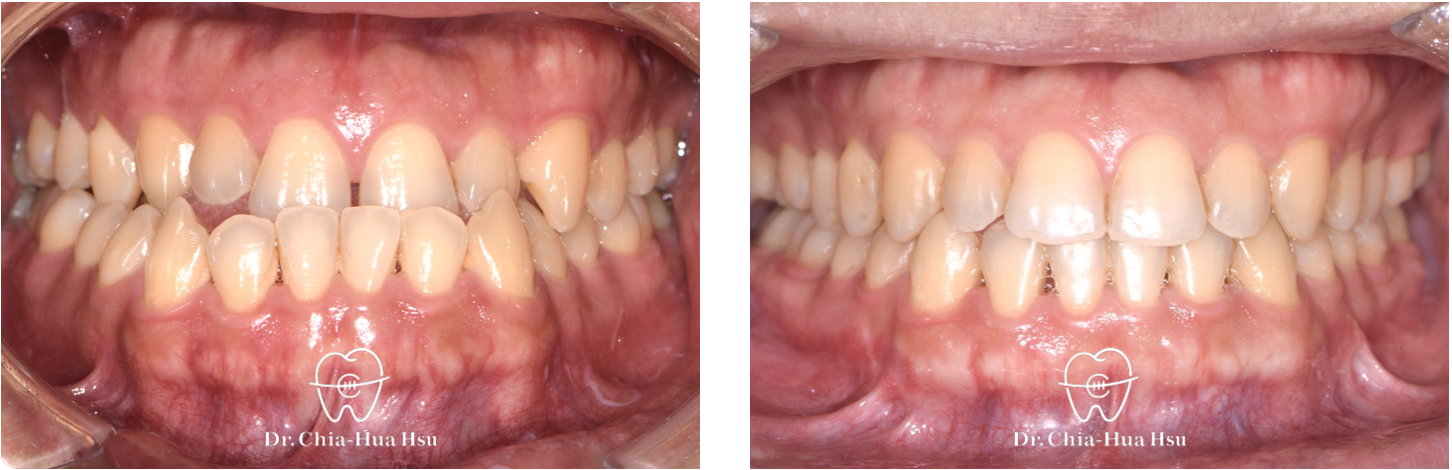

- 問題分析:患者是標準的骨骼三類咬合(Skeletal Class I)伴隨齒列不整齊。

- 治療方式:使用傳統金屬矯正器,合併單顎正顎手術治療。

- 治療時間:2 年 2 個月。

治療前

治療後